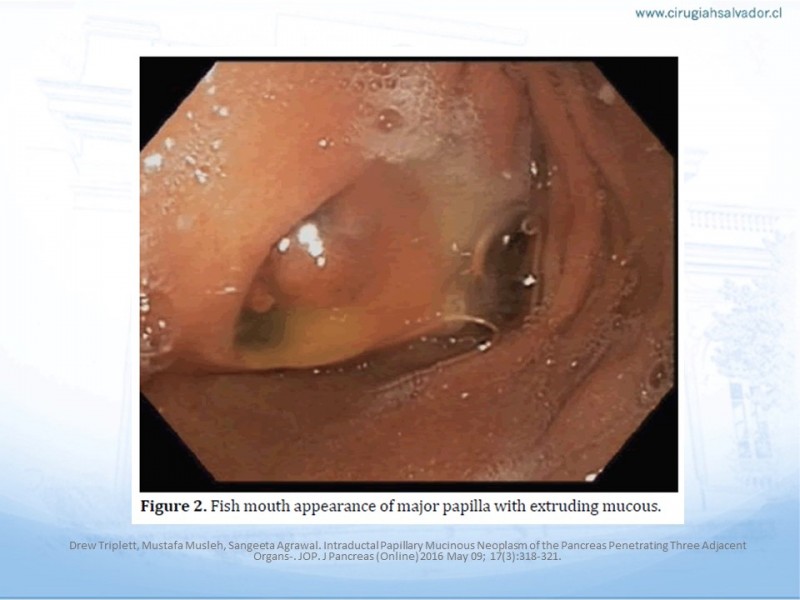

IPMN: Manejo